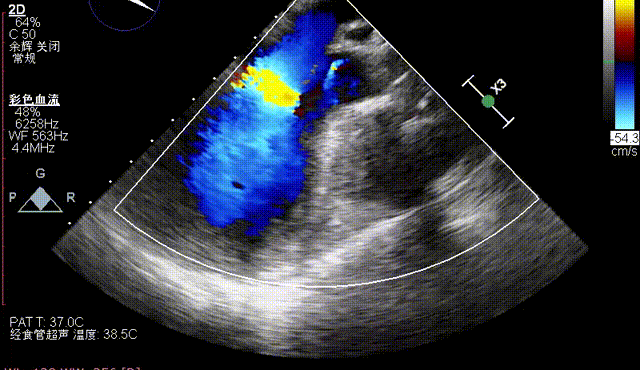

术后即刻评估

术后即刻TEE示主动面瓣膜最大峰值血流速为1.1m/s,平均跨瓣压差为2mmHg,少量瓣周漏。